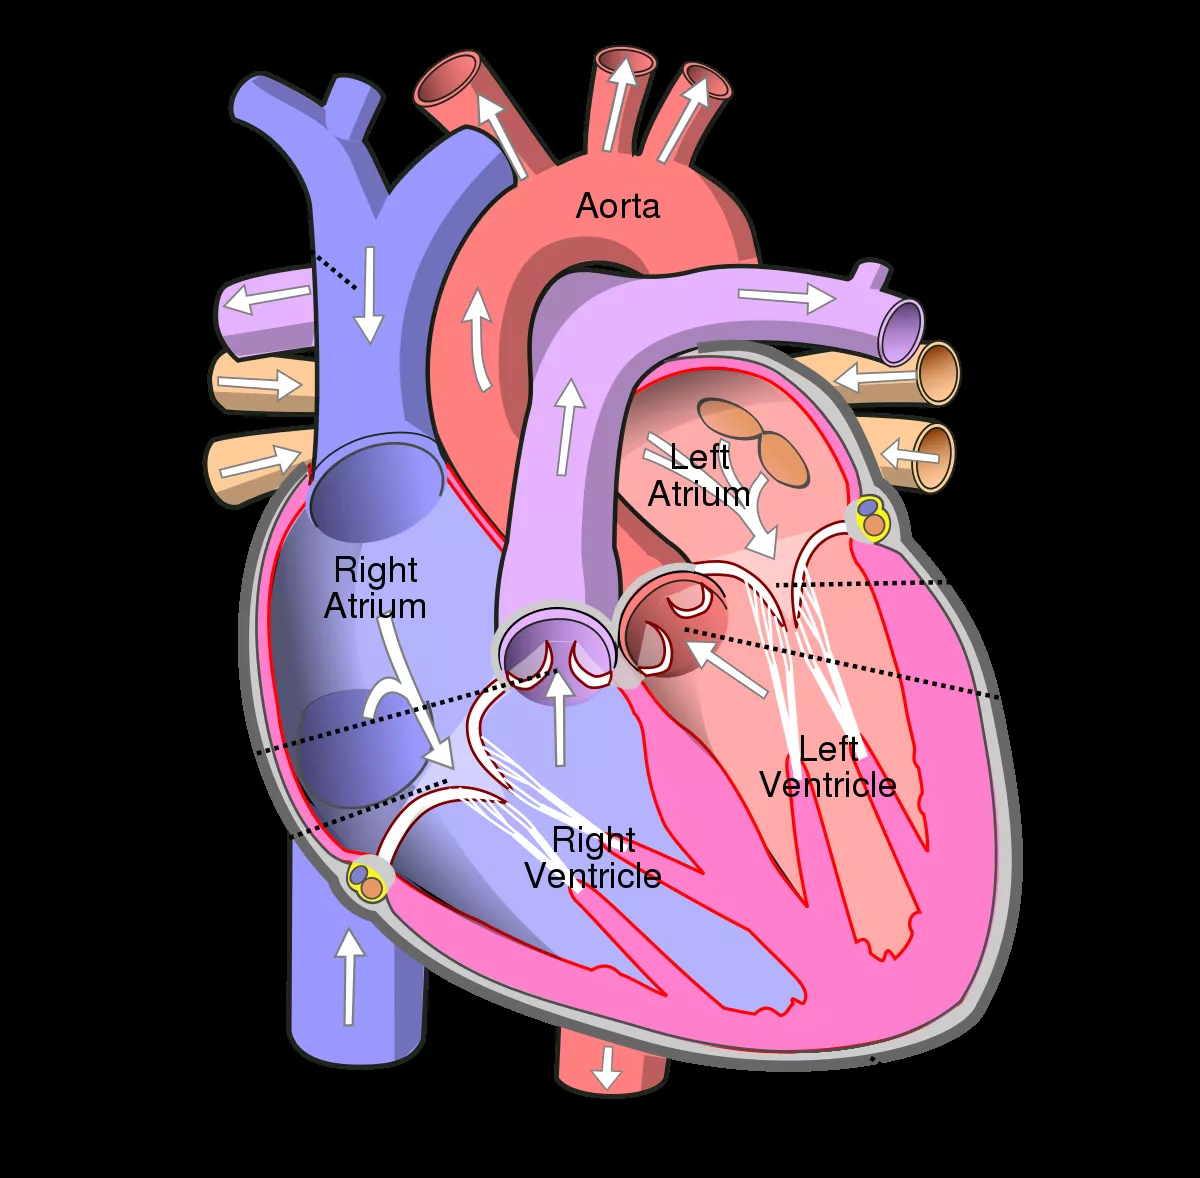

Human Heart Labeled Heart Diagram Human Heart Diagram Heart Blood Flow

Human Heart Biology